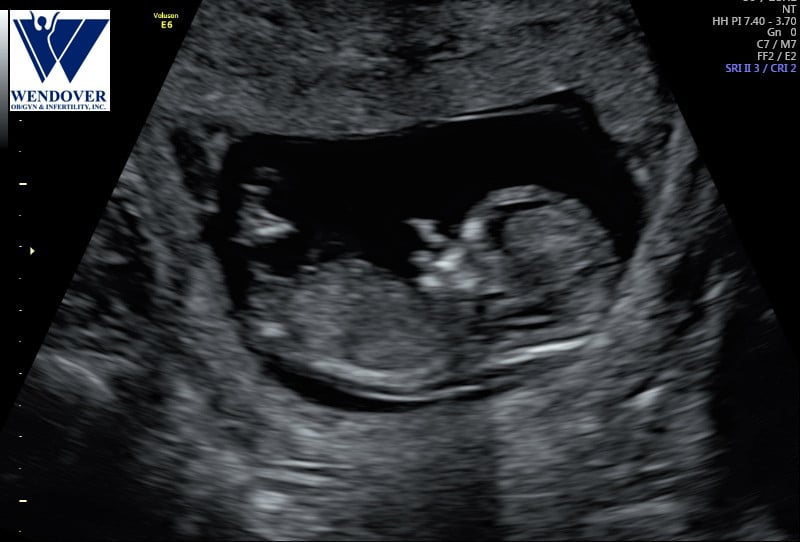

Soooo I don’t have my anatomy scan for another 2 weeks, but I’m 17 weeks with my 2nd pregnancy and not feeling a ton of movement-that’s worrying me because I’m scared I might have an anterior placenta. I know that it’s not a big deal, but I had an emergency c section and am planning an elective this time and I’ve heard anterior can cause problems with this. Soooo...does anyone know if this looks anterior or posterior? This was my 12 wk scan.

• The placenta is still developing at 12 weeks so sometimes it can be hard to see. But I’d have to say that looks anterior without scanning you myself.

I wouldn’t really worry about the placenta in reguards to the CS. Most of the time they move up higher in the uterus so it should be out of the way of a lower CS. But the doctors will have that assessed as your pregnancy progresses and go from there.